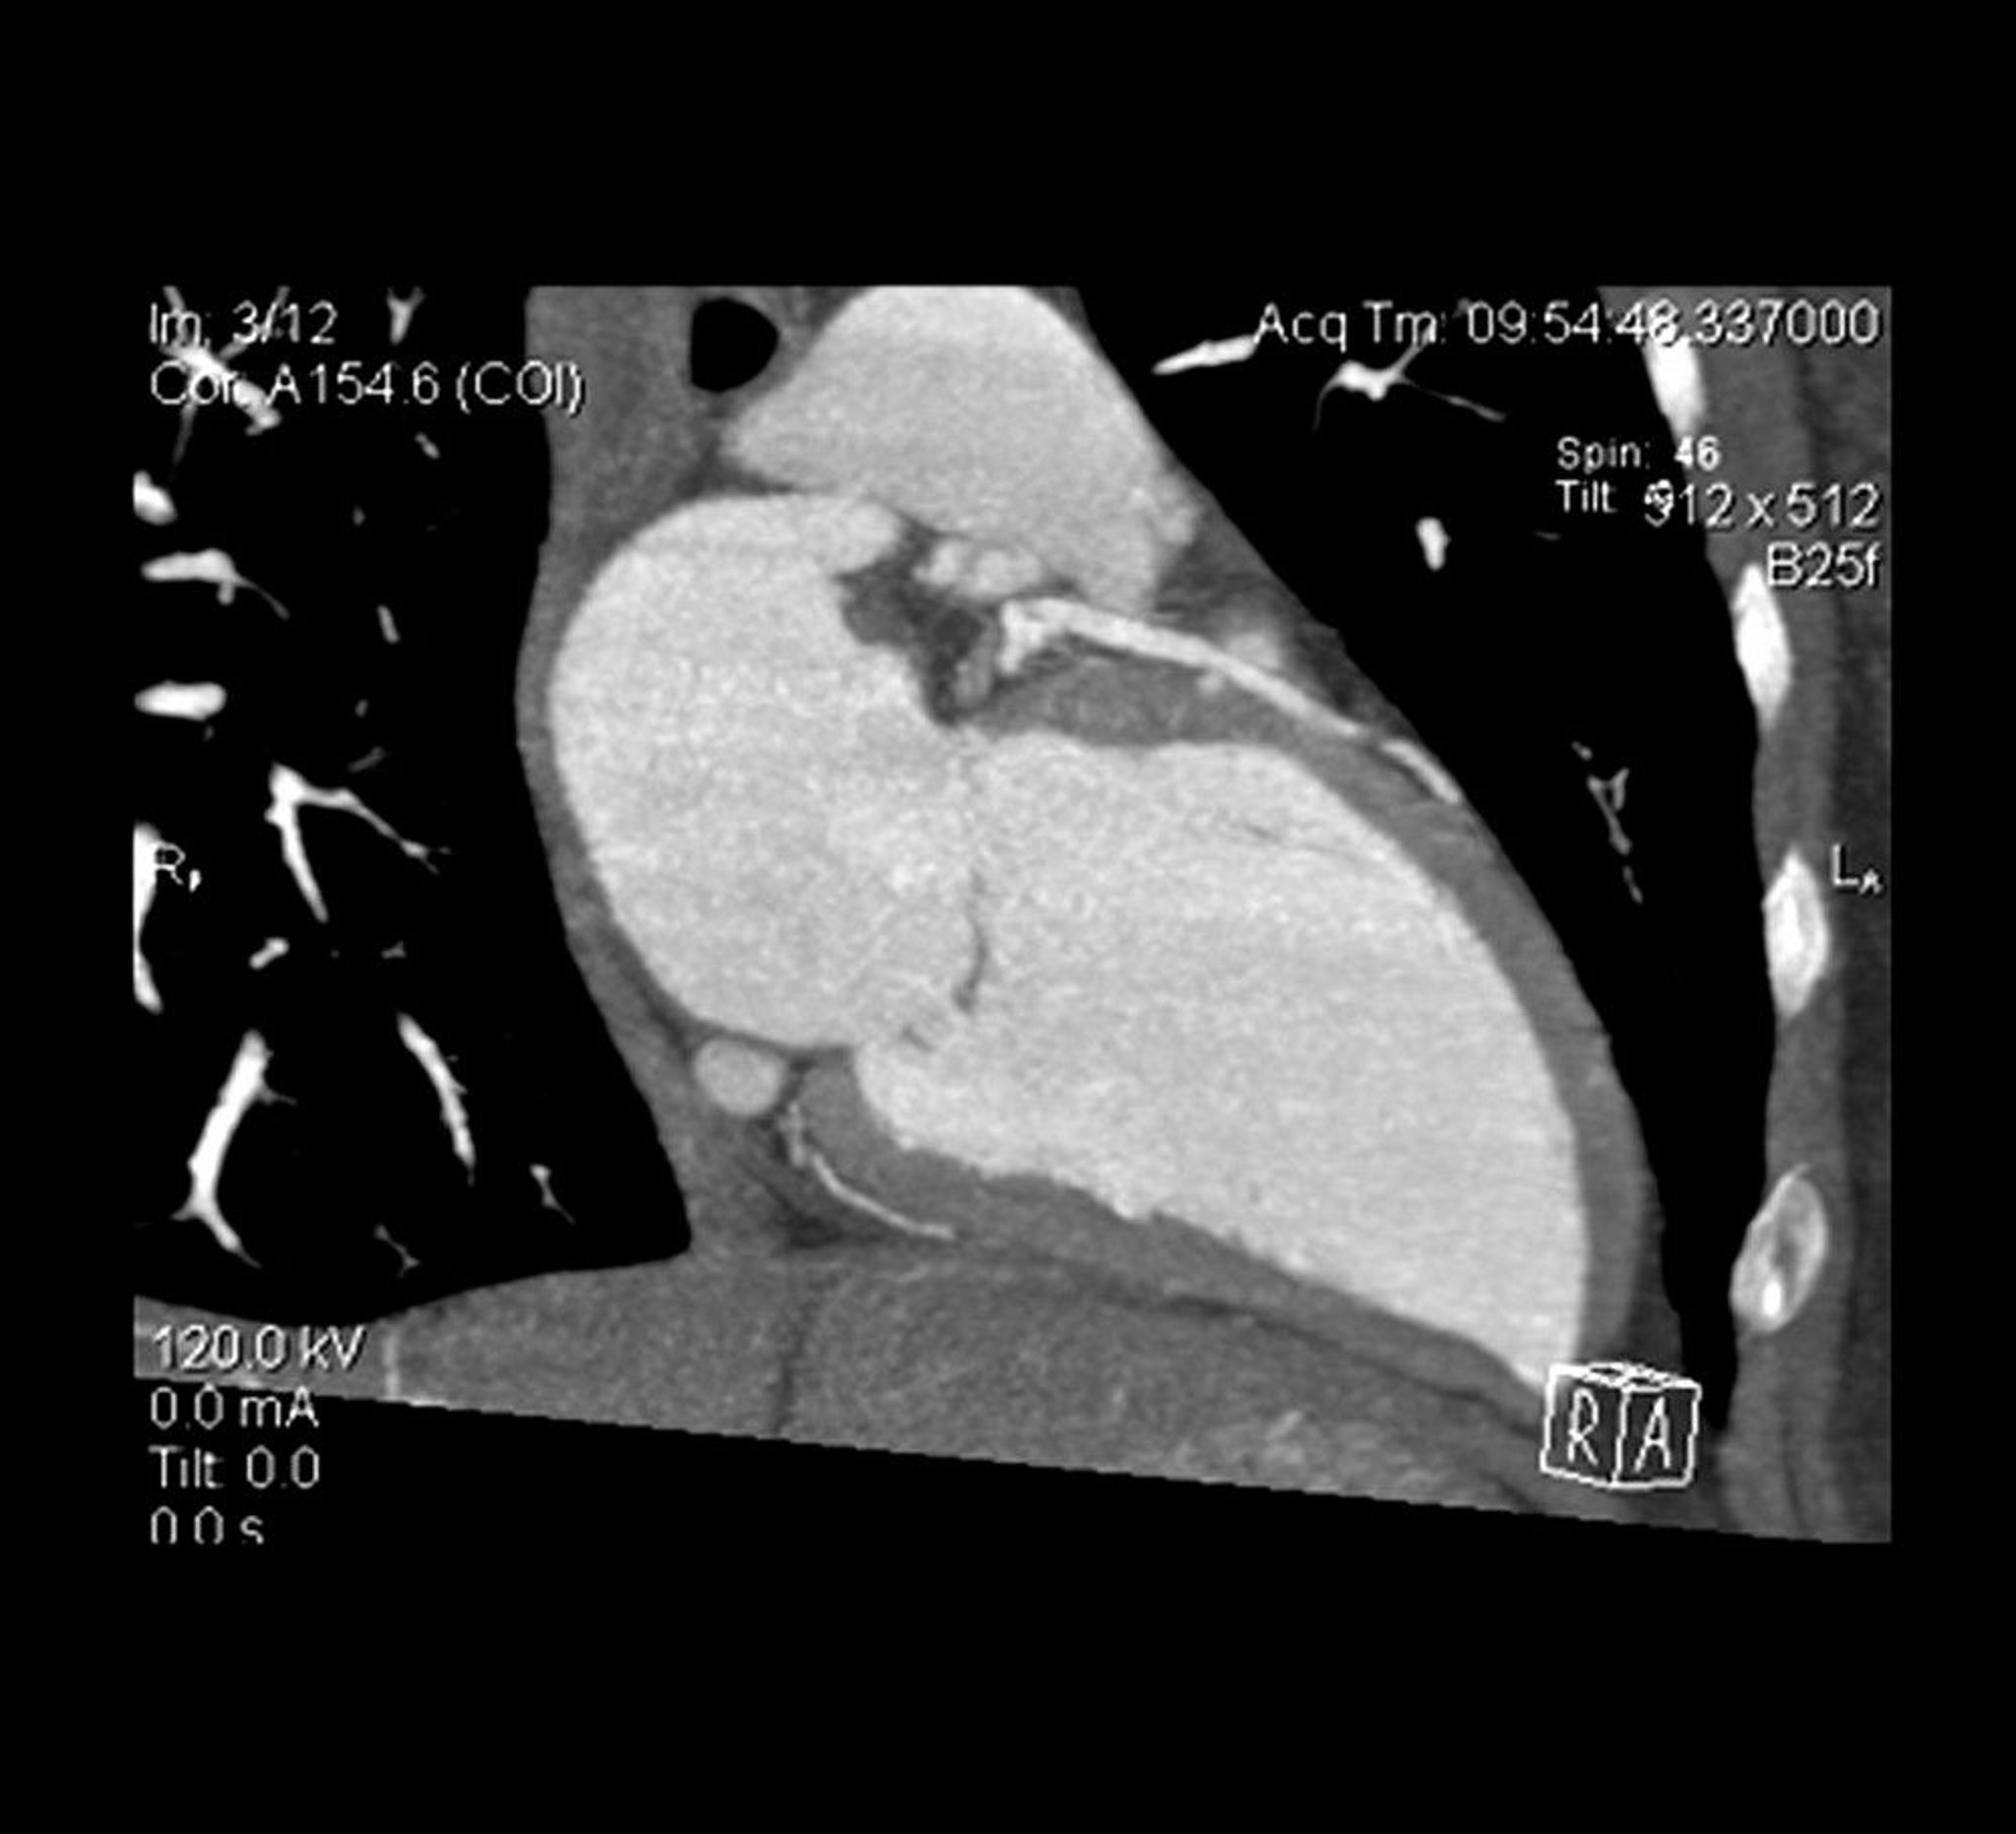

Cross sectional view of a cardiac CT angiogram shows the left ventricle and the left anterior descending artery.